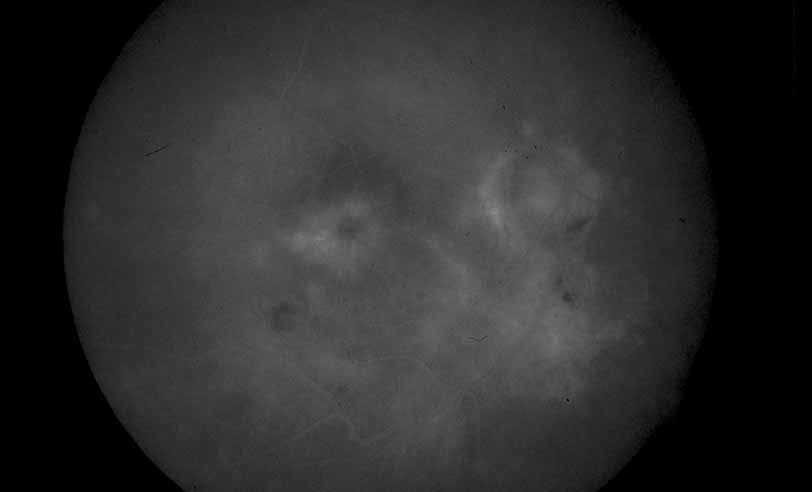

Fig. 26 Serpiginous choroiditis. Color photograph shows multiple scars of varying chronicity.

Fig. 27 Serpiginous choroiditis. Fluorescein angiography shows areas of hypofluorescence and hyperfluorescent staining at lesion edges.